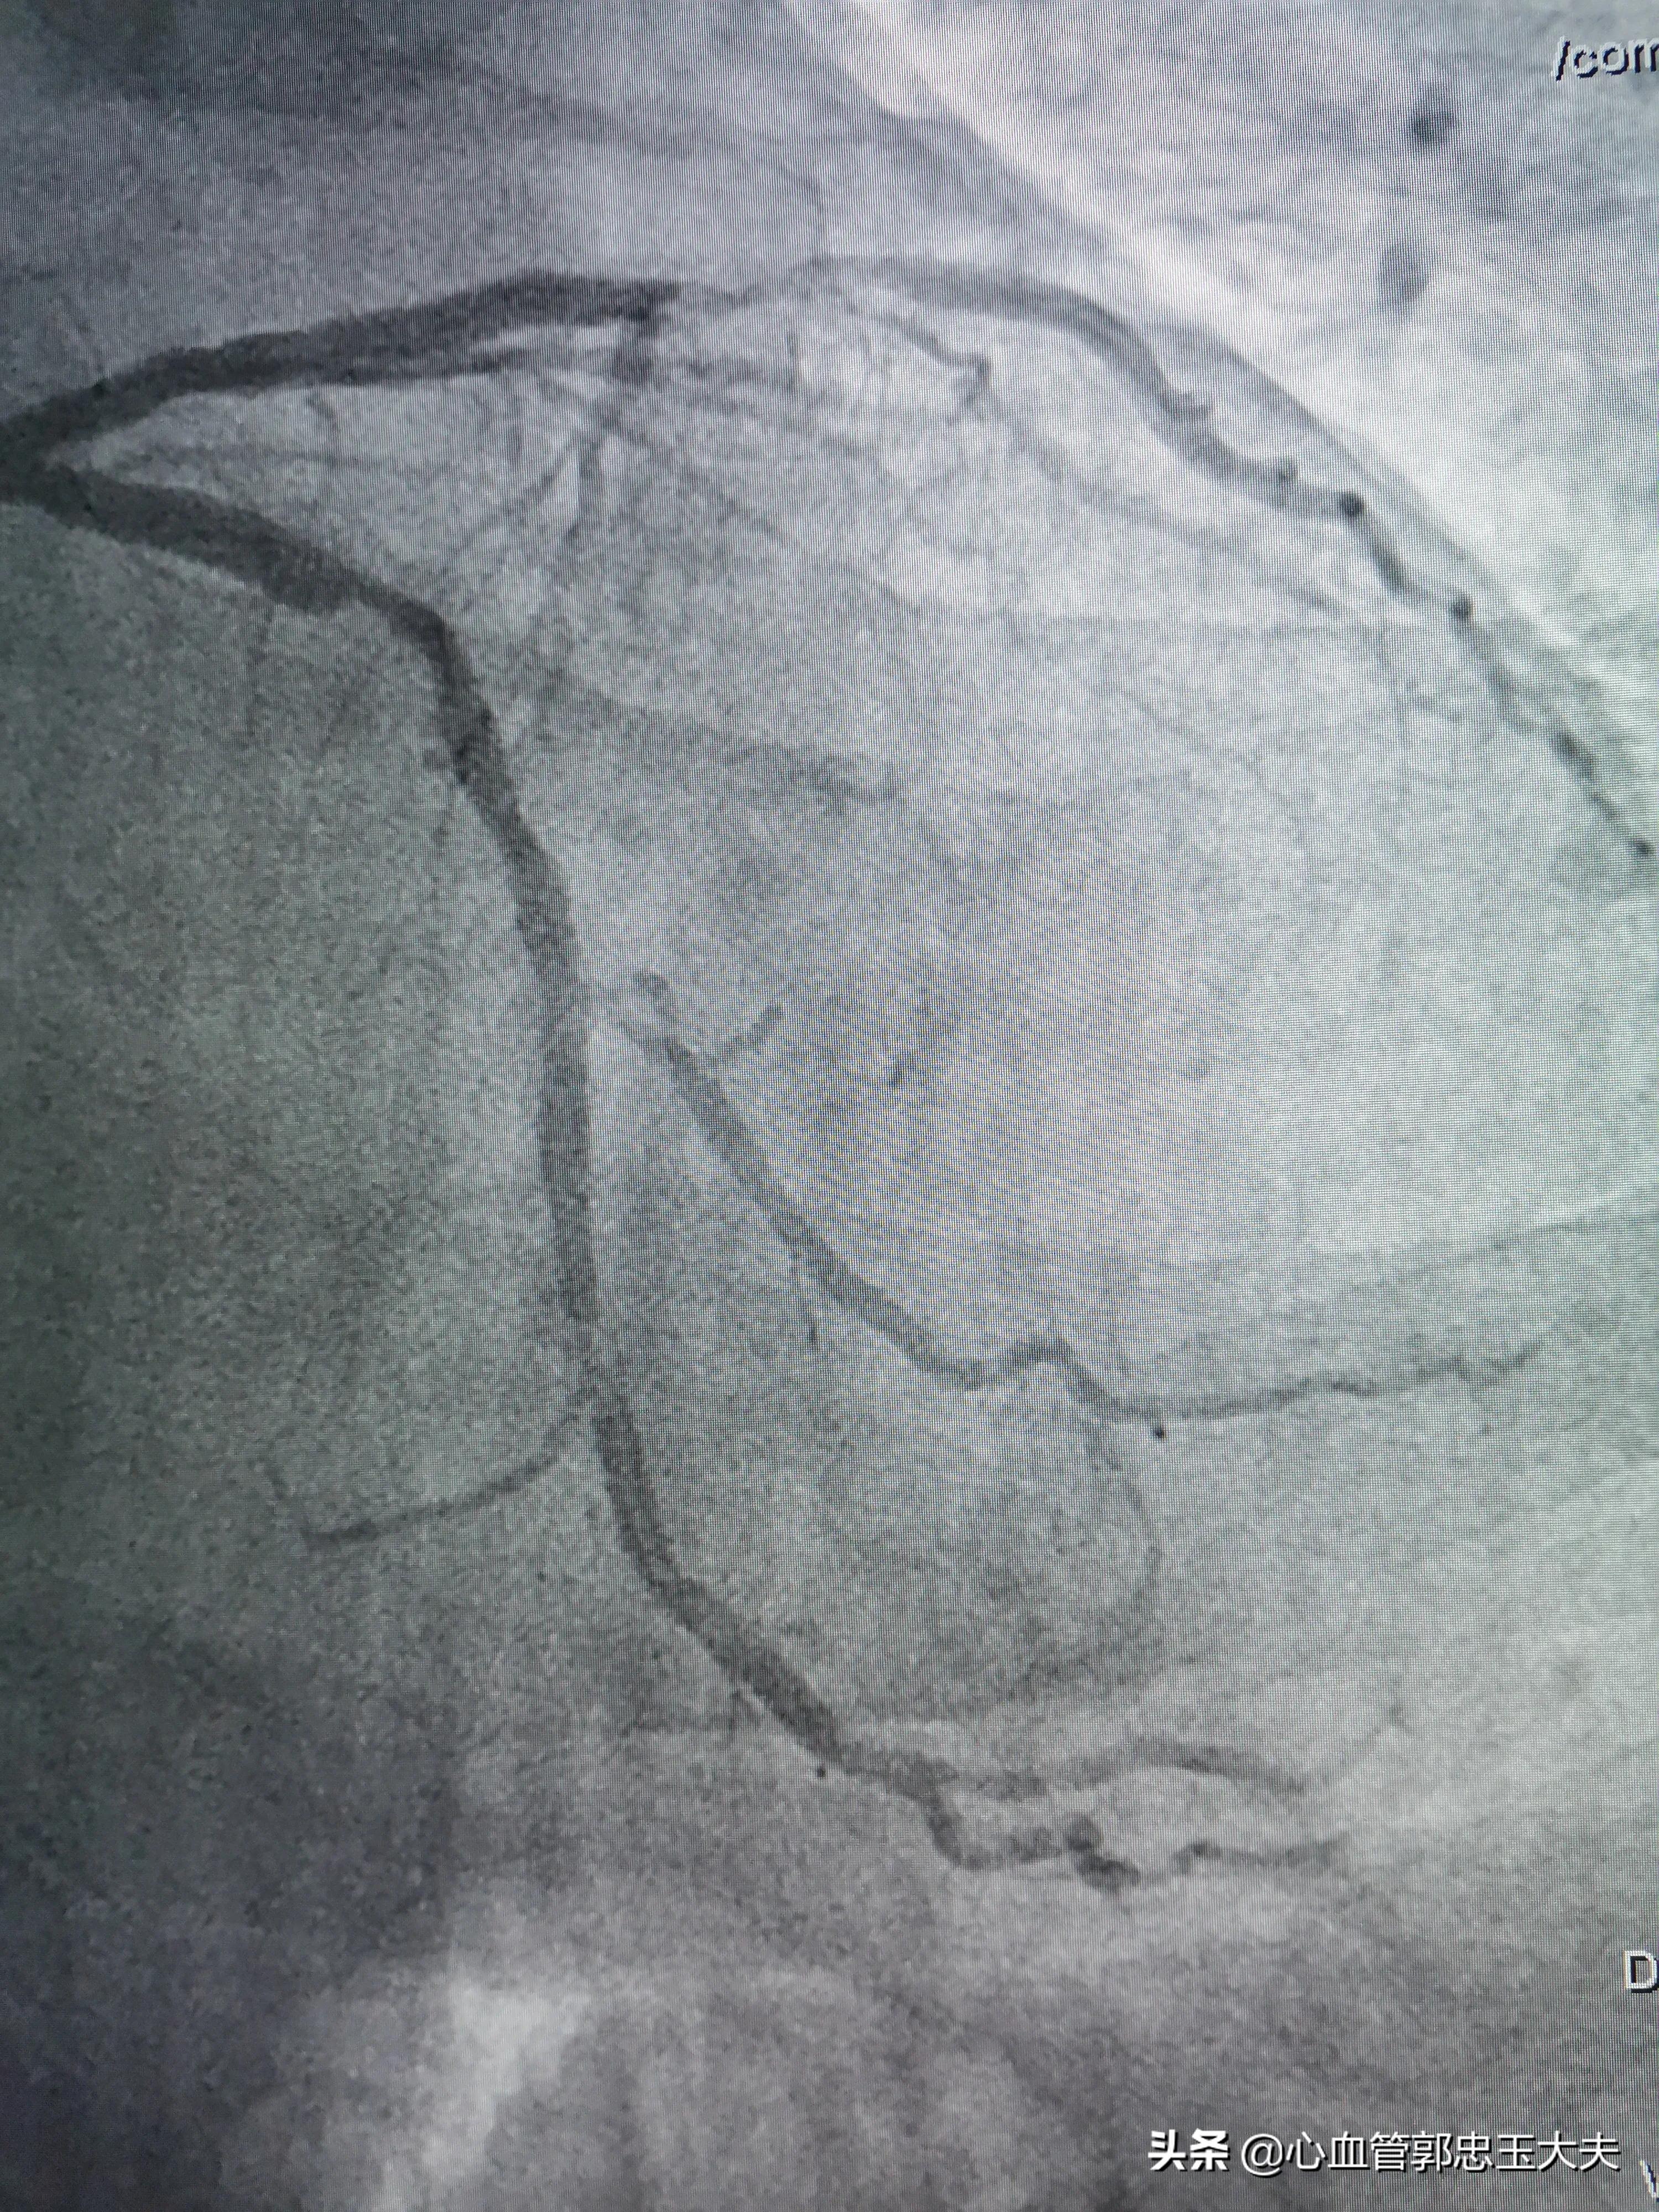

回旋支近段远端85~90%狭窄(如下图)